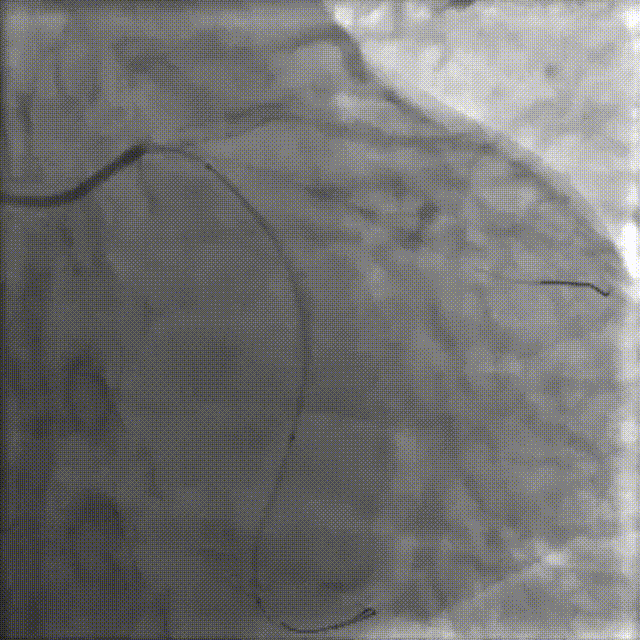

RCA—OCT术前检查

右冠开口ISR,最狭窄平均直径2.11mm;管腔面积 3.54mm²;以纤维斑块为主。